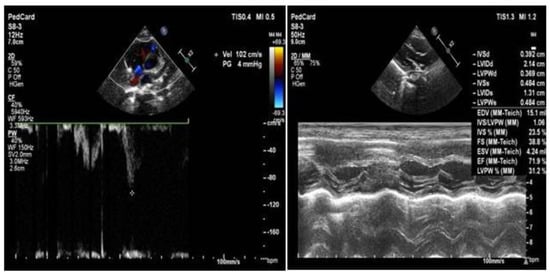

2. Case Report

2.1. Clinical Data